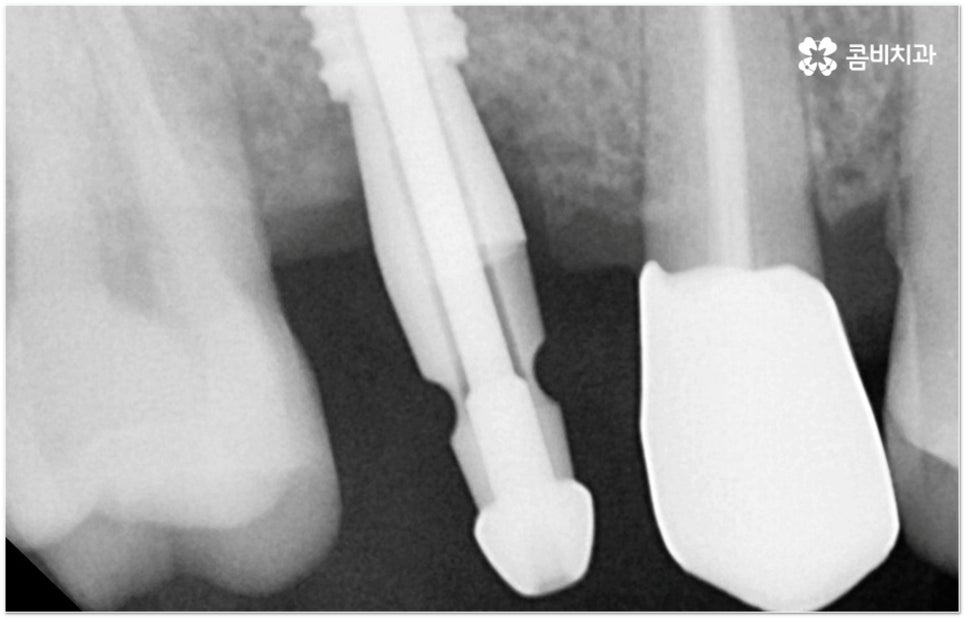

그러나 임플란트는 잇몸뼈에 직접 심어서 고정시키는 방식인 만큼 만약 환자분의 잇몸뼈가 부족하거나 치아가 빠진 후 오랜 시간이 지나 이미 잇몸뼈 소실이 상당 부분 이루어진 상태라고 한다면 먼저 골이식을 통해 이를 보충한 후 식립을 진행하는 뼈이식임플란트 방식을 이용할 필요가 있어요. 골이식 과정은 바탕이 되는 잇몸뼈의 밀도나 높이, 두께가 부족한 부분에 이식 재료를 심어주어 뼈를 재건해 주는 것인데 충분한 시간을 두고 무리하지 않게 진행하는 것이 뼈이식임플란트 수술의 성공률 및 안정적인 지속성을 높일 수 있는 방법이 될 거예요.

뼈이식임플란트 가 필요한지 살펴볼 때 3D CT 촬영과 같은 정밀 진단을 통해서 환자분의 잇몸뼈 두께 등 치조골 상태 뿐 만 아니라 구강 구조, 치아 및 잇몸 상태, 신경관 위치, 상악동까지의 거리 등을 꼼꼼하게 확인하여 치료 계획을 세우고 필요하다면 구강 질환에 대한 치료나 상악동 거상술 등을 선행하며 잇몸뼈 부족에 대해서도 골이식 과정을 먼저 진행하게 되는데요, 이러한 뼈이식임플란트 시술은 상당히 고난도의 복잡한 치과 진료인 만큼 관련 임상 경험이 풍부한 의료진과 함께 하는 것이 굉장히 중요하며 또한 수술 후 관리 면에서도 더욱 신경을 써 주시길 당부드리고 있어요.